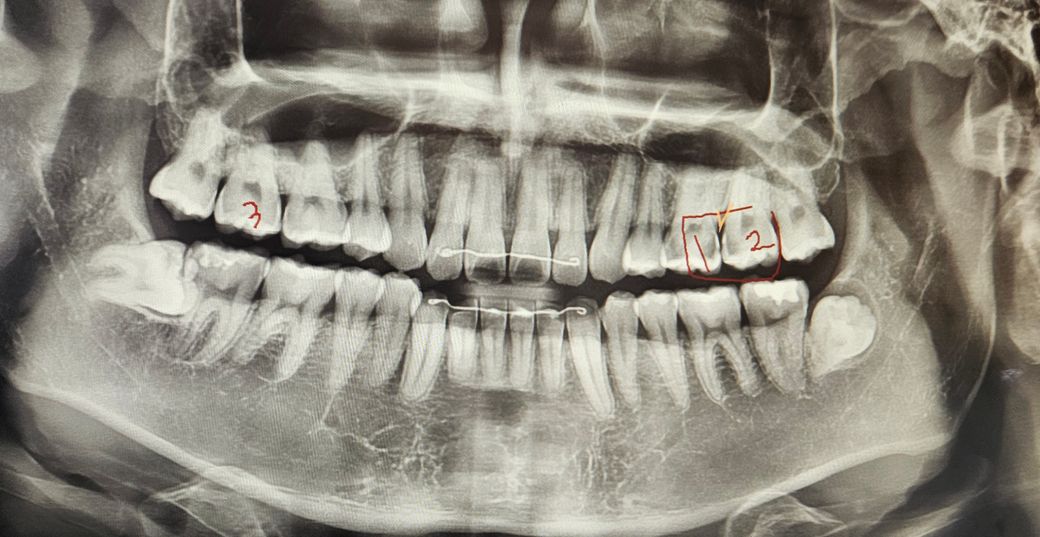

사진에 보이는 1,2번 치아 신경치료가 필요한가요?... 어느정도인지 알려주시면 감사할거같습니다 어떻게 생각하시나요?:)

• 1번 째 사진

사진으로 봤을 경우에 충치가 깊게 생긴 것으로 보입니다 충치를 제거했을 때 신경이 노출되거나 신경이 민감해질 수 있다면 신경치료를 하는 것이 좋습니다 신경치료의 가능성이 높을 것으로 생각됩니다

엑스레이 상으로 봐도 치아 사이에 충치가 많이 진행된거 같습니다. 둘다 신경치료를 하셔야될것같습니다.

인접면 충치로 2개 치아 사이에서 충치가 생긴 것으로 인접면 충치는 신경치료 해야 하는 경우 많습니다. x-ray 사진으로 보아 안쪽으로 많이 진행되어 신경치료 가능성 높아 보입니다.

위 사진만으로는 판별을 하기는 어렵습니다. 인레이 치료 혹은 신경치료가 필요할 것 같습니다.

충치가 다소간 관찰되고 해당 충치가 깊어 신경을 자극했을 경우 신경치료 가능성이 있어보입니다